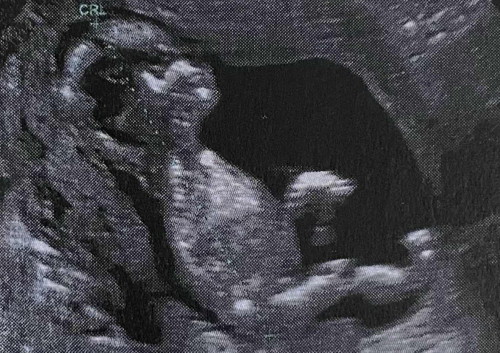

แม่ๆคนไหนมีภาวะแท้งคุกคามบ้างคะ แล้วดูแลตัวเองกันยังไงบ้าง แม่พึ่งมีภาวะแท้งคุกคามตอน17วีค ค่ะตกใจมากๆ แต่ซาวน์ดูน้องปกติดี หัวใจเต้นปกติเลย รกและมดลูกก็ปกติดีหมดเลยค่ะ #คุณแม่ๆช่วยแนะนำหน่อยค่ะ #ขอบคุณสำหรับคำตอบค่ะ